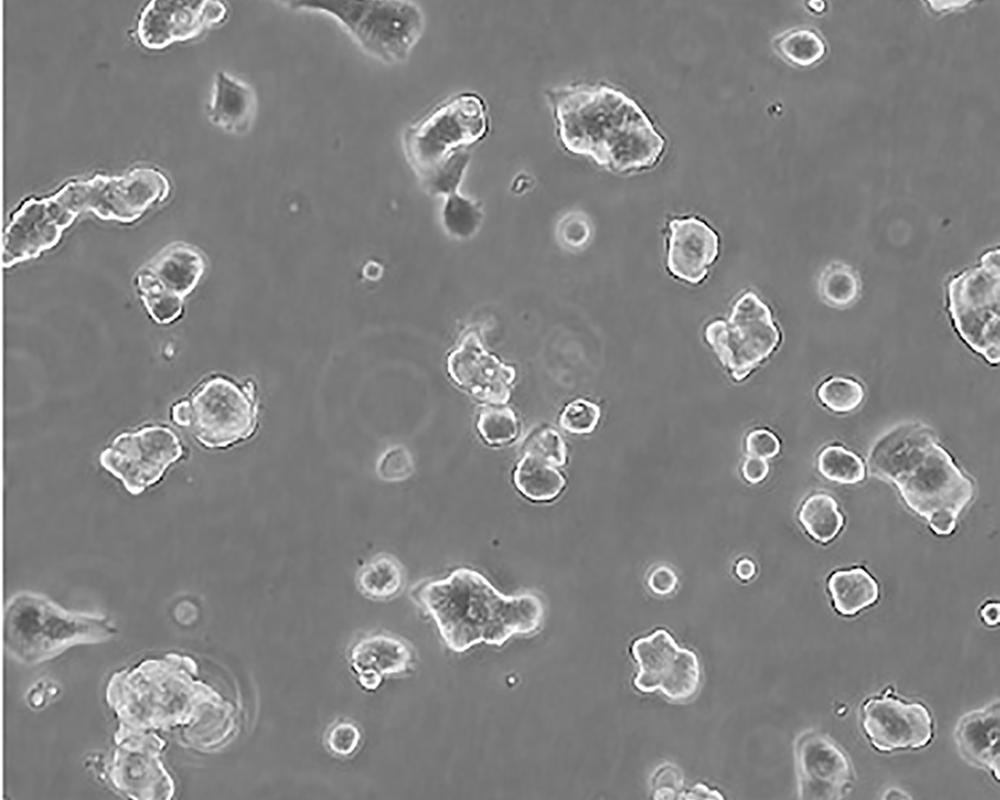

產品名稱 ZR-75-1 [ZR751]

商品貨號 MZ-0194

中文名稱 人乳腺癌細胞

組織來源 浸潤性導管癌;腹水轉移;女性

生長特性 adherent

形態特征 epithelial

細胞描述 該細胞產生高水平的黏液素MUC-1 mRNA,低水平的MUC-2 mRNA,但不表達MUC-3基因;表達雌激素受體。